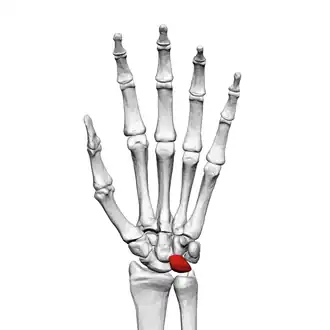

![]() Left hand anterior view (palmar view). Lunate bone shown in red. | |

The lunate bone (semilunar bone) is a carpal bone in the human hand. It is distinguished by its deep concavity and crescentic outline. It is situated in the center of the proximal row carpal bones, which lie between the ulna and radius and the hand. The lunate carpal bone is situated between the lateral scaphoid bone and medial triquetral bone.

Structure

The lunate is a crescent-shaped carpal bone found within the hand. The lunate is found within the proximal row of carpal bones. Proximally, it abuts the radius. Laterally, it articulates with the scaphoid bone, medially with the triquetral bone, and distally with the capitate bone. The lunate also articulates on its distal and medial surface with the hamate bone.[2]: 708 [3]

The proximal surface of the lunate bone is smooth and convex, articulating with the radius. The lateral surface is flat and narrow, with a crescentic facet for articulation with the scaphoid bone. The medial surface possesses a smooth and quadrilateral facet for articulation with the triquetral bone. The palmar surface is rough, as is the dorsal surface. The dorsal surface is broad and rounded. The distal surface of the bone is deep and concave.[4]